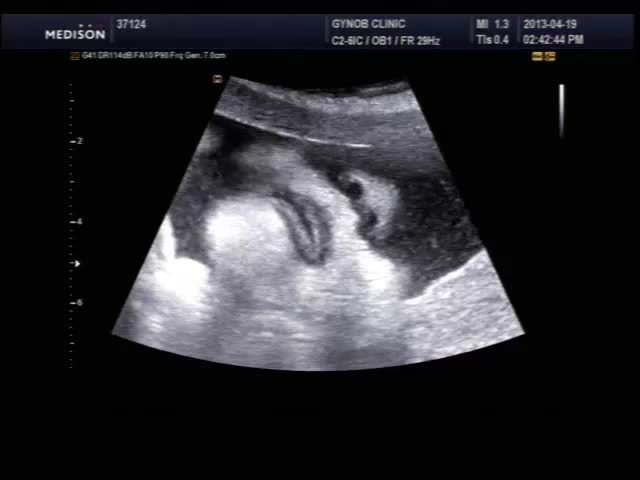

오늘 초음파 보신 산모의 영상인데 태아의 입과 인중 부분이 잘 보이는 편이라 여러분들께 보여드릴 겸, 그리고 설명 드릴 것도 있고 해서 올려 봅니다.

초음파 검사시 태아의 입과 인중을 살펴보는 것은 구순열과 같은 기형이 있는가 보는 목적이며 요즘은 초음파 장비 기술이 발달하여 비교적 쉽게 중기에 진단이 가능합니다.

태아는 뱃속에서도 보고 듣고 먹고 다 할 수 있는데 위 영상을 보시면 태아가 입을 오물거리면서 무언가를 말하는 것도 같지만 사실 말을 하는 것은 아니고 음식을 먹는 운동을 하면서 실제 양수를 삼키는 모습입니다.

양수는 자궁벽의 삼출물로도 일부 구성되지만 대부분은 태아의 소변으로 만들어집니다.

그러니까 태아가 자신이 본 소변을 먹는다고 생각하면 조금 그렇기는 하지만 태아에게 있어 양수는 매우 중요한 기능을 합니다.

양수의 주 역할은 외부 충격에 대한 보호 작용을 하는 완충역이지만 그것 못지 않게 중요한 것이  태아의 폐성숙을 촉진하는 것입니다.

따라서 양수가 너무 부족하게 되면 태아의 폐성숙이 느려져서 나중에 출산하고 나서도 호흡 기능이 원할하지 않을 수가 있습니다.

태아의 입이나 코를  통하여 폐로 들어간 양수는  폐세포를 확장시키고 폐세포가 산소 공급을 잘 해낼 수 있도록 성숙시키는 작용을 합니다.

위장으로 들어간 양수는 흡수되어 혈액 내 수분으로 공급되기도 합니다.

여하튼 그리고 그런 흡입 운동 덕분에 태어나서도 바로 젖꼭지를 빨고 모유를 먹으려 하는 행동을 보이게 되는 것이기도 합니다.

그러니까 태아에게 양수는 자신이 거주하는 집이자 외부의 충격과 환경의 변화를 완충시켜주는 옷이자 항상 먹고 마시는 음식입니다.

즉 의식주 그 모든 것이라는 뜻입니다.